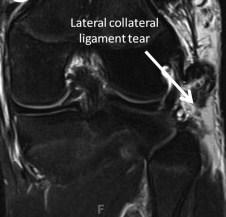

젊고 운동하는 환자분들 중에 생길 수 있는 무릎 외측 인대 손상 입니다. 무릎안쪽에서 바깥쪽으로의 외력이 작용하는 것을 VARUS STRESS 라고 하는데, 이러한 과도한 VARUS STRESS 가 짧은 순간에 가해진 경우 이런 바깥쪽 인대의 손상이 있을 수 있습니다.

외측인대는 앞측 비골 근위부와 원위 대퇴골(lateral epicondyle) 사이에 붙어있습니다.

주변에 삼출물이나, 다른 조직 PLC, ACL, PCL 등이 손상되진 않았는지 확인해야합니다.